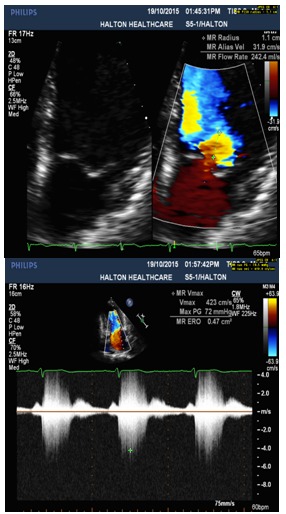

5. Eccentric anteriorly directed severe MR jet area over 50% (Figure 2) with MR ERO 0.47cm2 (Figure 3) and Vena Contracta 0.76cm (Figure 4), which is consistent with posterior flail leaflet of MVP.

Figure 3: PISA: large flow convergence radius 1.1cm(Left) with MR ERO 0.47 cm2 and dense, early peaking and triangular CW Doppler MR jet(Right).

Physical examination and 2-dimensional (2D) echocardiography are the diagnostic gold standards for MVP [4]. According to echo findings I listed above, together with the patient’s symptoms (SOB and chest discomfort) and pansystolic murmur heard at the apex, the patient was diagnosed as severe MVP with flail posterior leaflet. Echo criteria of flail leaflet includes leaflet tip pointing to LA without systolic coaptation (Figure 1,2,4), torn chordae, double contour (parallel sign) between flail and normal leaflets (Figure 4), and eccentric MR jet direction opposite to the location of the flail leaflet (Figure 2 and 4) [3,4]. Doppler echocardiography is essential in determining the severity of MR. According to ASE guideline, criteria for severe MR includes a vena contracta width ≥ 0.7 cm, large central mitral regurgitation jet (area >40% of left atrium), pulmonary vein reversal, effective regurgitant orifice >40 mm2 and others [3,5]. The echo findings and Doppler measurements strongly support a severe MR in the patient (Table 1).

Large flow convergence 0.9cm at Nyquist of 40cm/s

1.1 cm at 31.9cm/s converted to 0.98cm at 40 cm/s

EROA ≥ 0.4 cm2

0.47 cm2